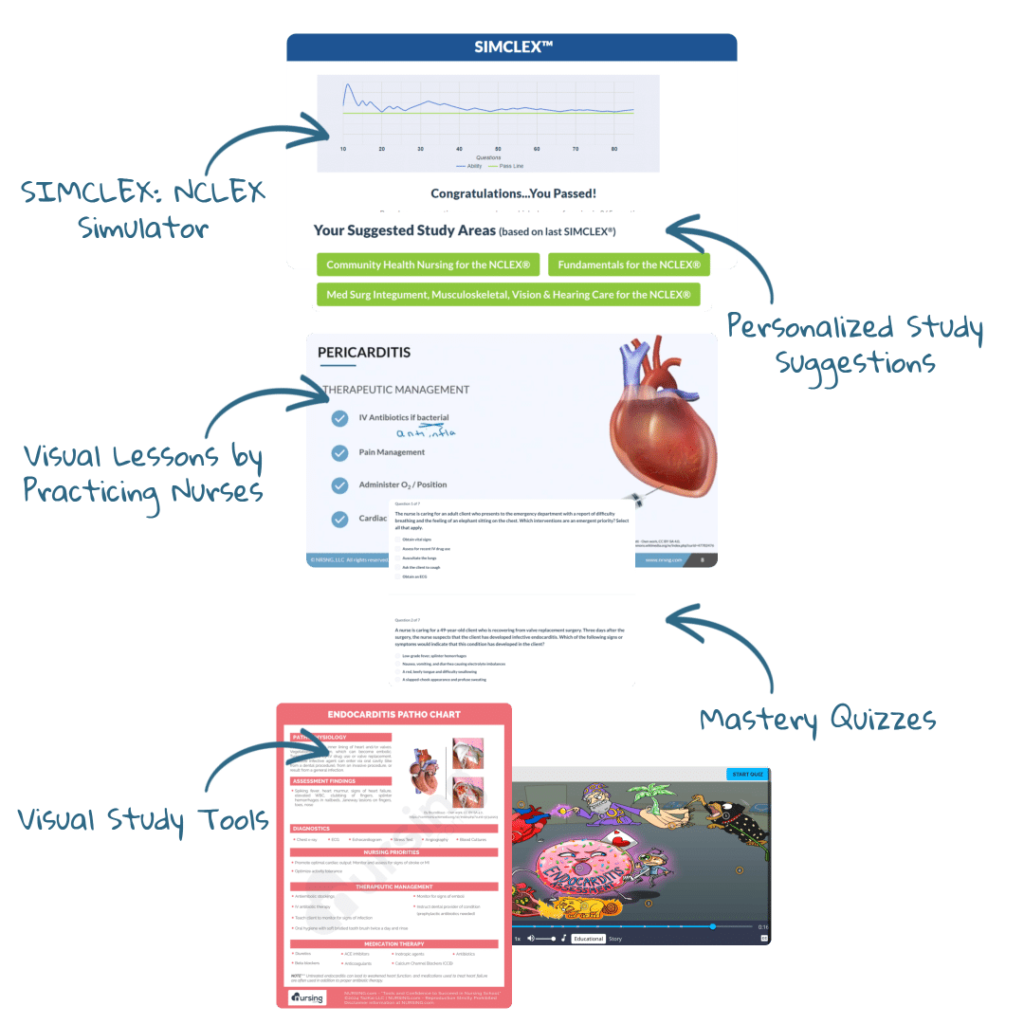

Study Tools

Cheatsheets

Mnemonic

Image

Picmonic